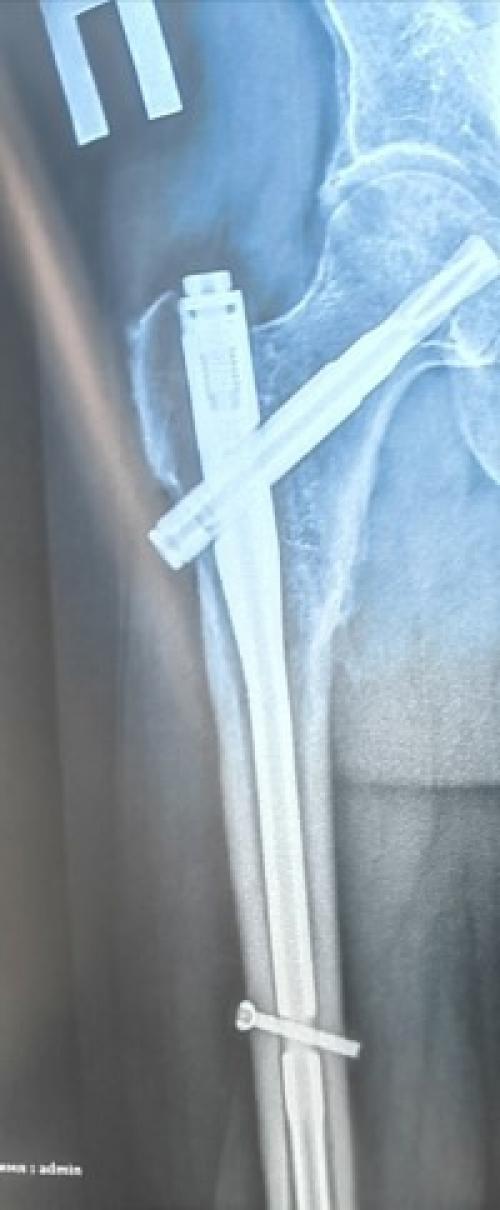

Как говорится, упал - очнулся - гипс. Только у меня не гипс, а осколочный перелом бедра со смещением. Помните как в мультике "Ну Погоди" лежал с подвешенной ногой на гирьке. Вот и я так же оказал в конце августе в больнице неделю с подвешенной ногой, потом операция. Как оказалось государство у нас не спонсирует операции на бедре, только шейке бедра. А вот если сломал бедро у тебя 2 варианта. Консервативный - это лежать, с вытянутой ногой с гирей и постоянными болями месяца 2-3. Потом снимают гирю и закатывают по пояс в гипс и так лежать ещё 2-3 месяца. И второй вариант делать платную операцию вставляя титановые штифты, но зато после операции в первый день уже на костылях можно двигается. Конечно, выбрала второй вариант. В первый же день после операции начала делать гимнастику как советовал врач в больнице, через неделю дома продолжила увеличивать нагрузку с фитнес резинками, тут знания фитнес тренировок помогли устроить для себя самой реабилитационный курс. И через 3. 5 месяца я откинула костыли. И как я понимаю это я ещё легко отделалась срастание у всех по-разному и на костылях ходят 4-6 месяцев. Кстати вопреки физике если ходить с одним костылем то его держать надо со стороны здоровой ноги, а не больной, тоже пришлось учиться. Сейчас похрамываю, но даже при том, что делала регулярно гимнастику на ногу мышцам все равно нужно восстановиться. Ну а через год снова операция и вынимать титановые штифты, врачи убеждают, что там все проще будет.